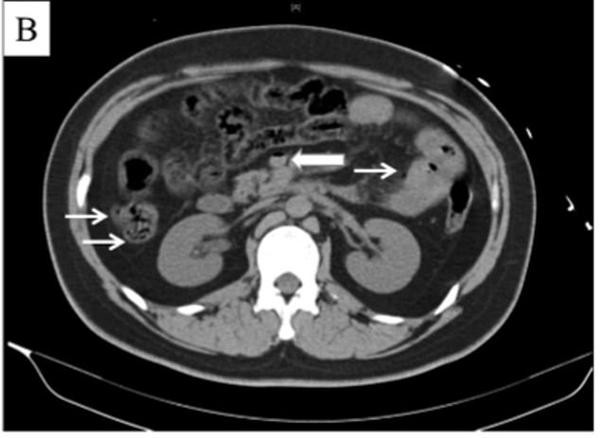

Việc chụp chiếu sau đó đã cho thấy anh này bị trướng khí trong ruột và tĩnh mạch cửa, và bị một tình trạng gọi là “sốc gan”, tức là tổn thương do thiếu oxy đến gan.

| Khí tích tụ ở thành ruột (những mũi tên mảnh) và tĩnh mạch mạc treo tràng trên (mũi tên đậm) của bệnh nhân. Ảnh: Mail Online. |